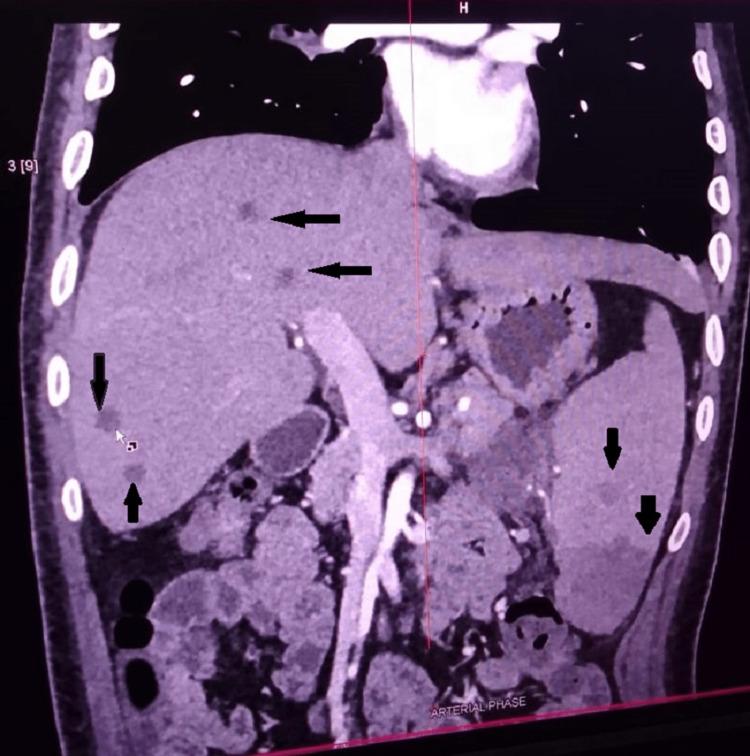

Melioidosis is caused by the Gram-negative bacilli Burkholderia pseudomallei, which is found in contaminated water and soil and spreads via inhalation, inoculation, and ingestion. Melioidosis manifests diversely in immunocompetent and immunocompromised patients, ranging from asymptomatic to life-threatening respiratory distress, septic shock, localized tissue infection, necrotizing pneumonia, and soft organ abscesses.  Methods: An 18-month observational study was conducted at a tertiary center in central India among various confirmed melioidosis cases, with data gathered and analyzed. Aerobic culture and sensitivity were performed in all studied cases, either in blood/body fluid/localized collection - using blood agar media for the culture and disc diffusion method on Mueller Hinton agar for sensitivity. Other tests, such as radiological imaging, were conducted according to symptoms and signs of localized infection.

类鼻疽由革兰氏阴性杆菌伯克霍尔德菌属假鼻疽杆菌引起,该菌存在于受污染的水和土壤中,可通过吸入、接种和摄入传播。类鼻疽在免疫功能正常和免疫功能低下的患者中表现多样,从无症状到危及生命的呼吸窘迫、感染性休克、局部组织感染、坏死性肺炎和软组织脓肿。